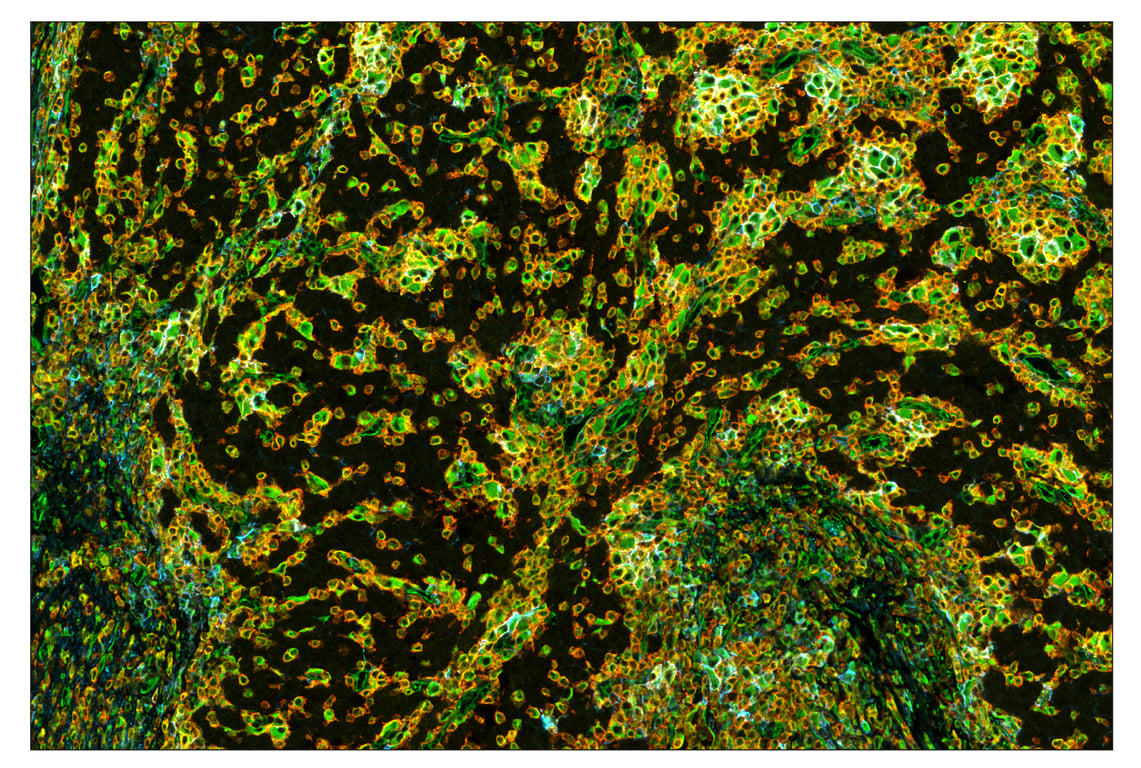

SIRP alpha/SHPS1 (D6I3M) & CO-0034-594 SignalStar Oligo-Antibody Pair #60004

SIRP alpha/SHPS1 (D6I3M) Rabbit Monoclonal Antibody (SignalStar™ Conjugate 0034) recognizes endogenous levels of total SHPS1 protein. This antibody recognizes both large and small isoforms of murine mSHPS1/SIRPα.

Human, Mouse